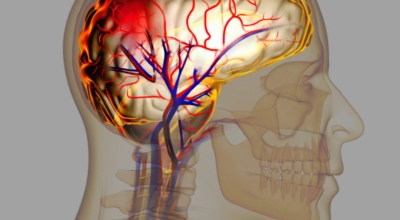

전 세계적으로 2초에 한명씩 발생하고, 6초에 한 명씩 사망하는 질병으로 국내에서도 3대 사망 이유가 되는 것 중 하는 뇌졸중. 뇌졸중은 뇌 일부분에 혈액을 주는 혈관이 막히거나 터지면서 발생하는 병으로 고혈압이 뇌졸중의 대표적인 까닭 질환입니다. 뇌졸중은 뇌혈관이 막히거나 터져서 뇌세포가 훼손되서 생기는 신경학적 증상입니다.

뇌졸중은 뇌경색과 뇌출혈 두가지로 나뉘게 돼요. 먼저 뇌경색은 뇌혈관이 막혀 영양분과 산소를 주는 피가 통하지 않는 상태로 원은은 크게 세 가지로 나눌 수 있는데요 동맥경화증이 생겨 좁아진 부위로 인하여 혈액공급이 부족해지거나 좁아지다가 결국 막혀버리는 경우, 큰 혈관에서 분지한 작은 혈관들이 고혈압 등으로 압박을 받으면 혈관이 막히는 경우가 있습니다.

또한 심장 판막질환이나 심방세동 또는 심근병 등등의 심장 질환이 있는 경우 심장에서 혈전이 만들어지고 그게 뇌로 흘러가게 되면 뇌혈관을 막게 되는 경우가 있답니다. 뇌출혈은 뇌경색과 반대로 뇌혈관이 터져서 생기는 뇌내 출혈과 거미막하 출혈로 나누게 돼요. 거미막하출혈은 혈관벽의 약한 부분이 부풀어 오르는 뇌동맥류가 터지는 경우와 관련성이 크다고 해요.

육체의 혈액순환을 방해하는 모든 까닭이 뇌졸중의 까닭이 될 수 있답니다. 흡연과 음주 또한 뇌졸중의 까닭이 될 수 있다고 하며 고혈압, 당뇨, 비만, 고지혈증 또한 뇌의 혈액순환을 방해하고 뇌혈관 건강을 악화시키만드는 이유가 되는 것 중 1개로 보고 있답니다.